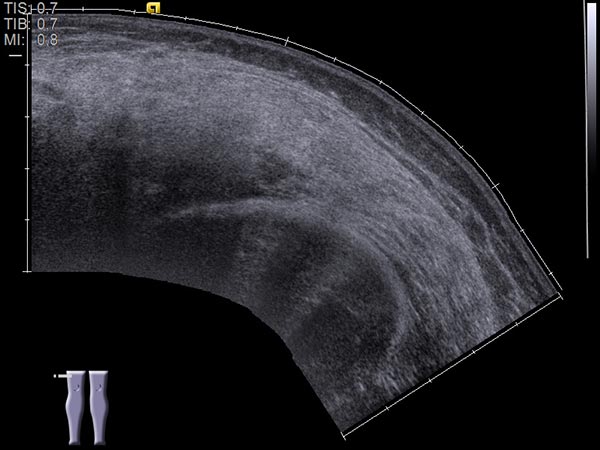

Ultrasound image (automatically assembled 2D image) before sclerotherapy. The cavities of the venous malformation are initially hypoechoic to echo-free. These cavities will be occluded by the inflammation induced by the sclerotherapy.

Ultrasound image (automatically assembled 2D image) after sclerotherapy. The hypoechoic cavities of the venous malformation are now occluded by the inflammation induced by sclerotherapy. The image now appears more homogeneous and echogenic on ultrasound. After occlusion of the cavities, painful thrombophlebitis can no longer occur.